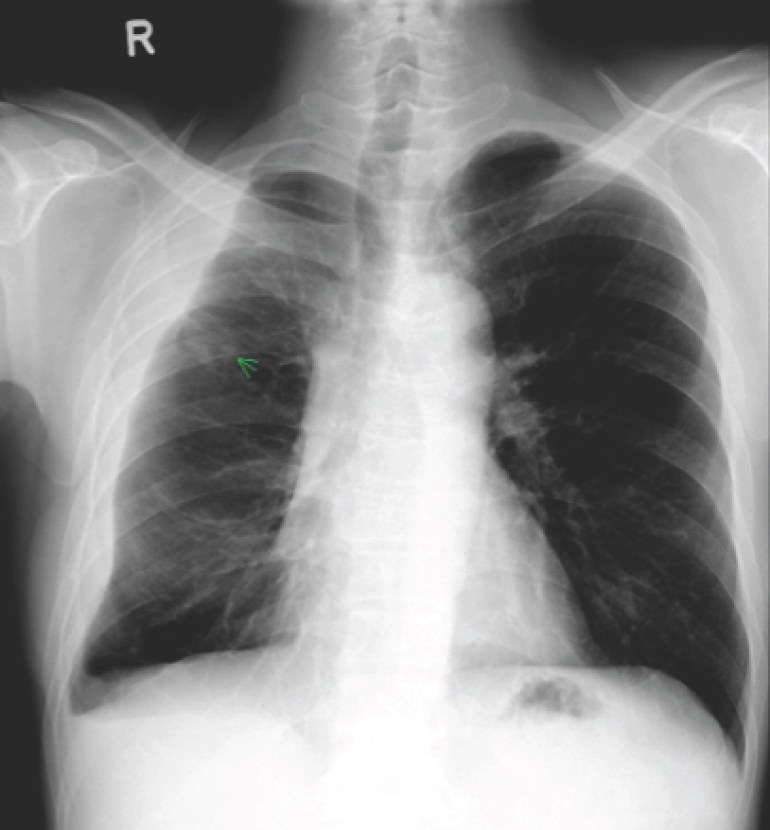

He felt clinically better after starting the anti-tuberculosis therapy, with no further fever nor shortness of breath (except on exertion), and had also started to gain weight. The pleural fluid culture was positive for Mycobacterium tuberculosis complex which was sensitive to all drugs. During the routine follow-up visit after completing 2 months of therapy, however, the chest X-ray was grossly abnormal.

Chest X-ray 2 months after starting anti-tuberculosis therapy, showing a massive right pleural effusion.

This patient had a loculated pleural effusion with radiological suggestion of a trapped lung. However, the massive increase in size of the pleural effusion 2 months after starting appropriate treatment is consistent with a paradoxical response to anti-tuberculosis therapy. This is now believed to be a immune reconstitution syndrome, and occurs in up to 15% of non-HIV patients but up to 25% of HIV-infected patients with concurrent tuberculosis who are started on highly-active anti-retroviral therapy (HAART). It occurs more commonly with extra-pulmonary tuberculosis, particularly cervical lymphadenitis and TB pleurisy.

Treatment of paradoxical response to anti-tuberculosis therapy is largely conservative, although steroids and/or surgical therapy are options if symptoms are severe. We offered the patient surgical drainage of the effusion in view of its massive size (potentially complicating respiratory function should any new lung infection develop), but he wisely refused. Subsequent chest X-rays showed gradual reduction in the size of the effusion over time, although it did not really disappear even at the time of stopping anti-tuberculosis therapy.